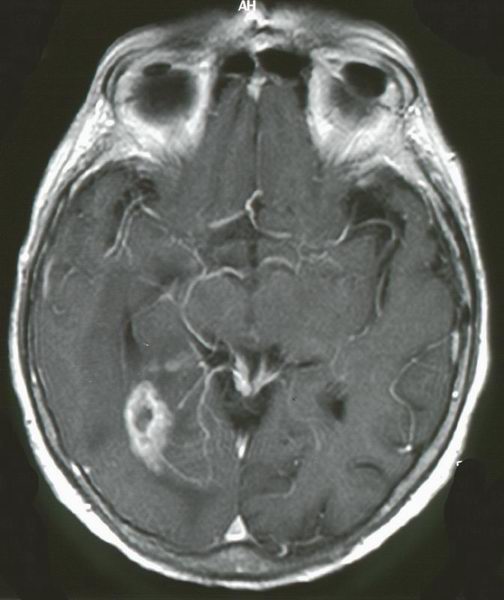

Das MRT zeigt ein kleinzelliges Glioblastom rechts temporo - occipital. Die Randbezirke des Tumors nehmen intensiv Gadolinium auf.